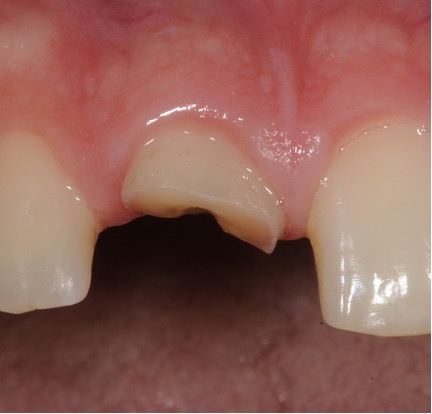

Fractured teeth

In this case a repeat root filling was completed. This is to minimise risk of infection from the exposed existing root filling. A fibre post and core was placed to build up the tooth sufficiently to retain a crown. This was then restored with an all ceramic crown. If there is insufficient tooth structure sometimes surgery can be carried out. In other cases it may not be possible to restore the tooth.